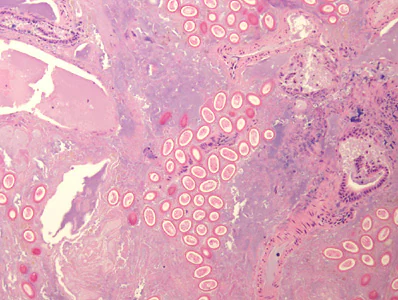

Several people developed gastrointestinal symptoms of watery diarrhea, nausea with vomiting, and low-grade fever approximately 1 week after attending a catered event. Stool specimens were collected for laboratory testing which included a formalin-ethyl acetate concentration with brightfield wet mount examination.